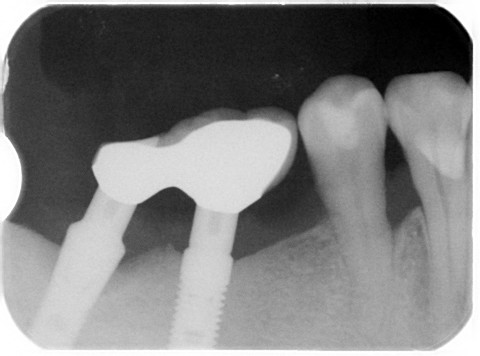

こちらの患者様は2002/02/21、16年前に当医院で私がインプラント手術致しました。16年後の定期健診でインプラント周囲炎を起こしていることを発見致しました。

レントゲン上で左のインプラント周囲の骨が吸収しているのが観察されます。(2018年2月撮影)